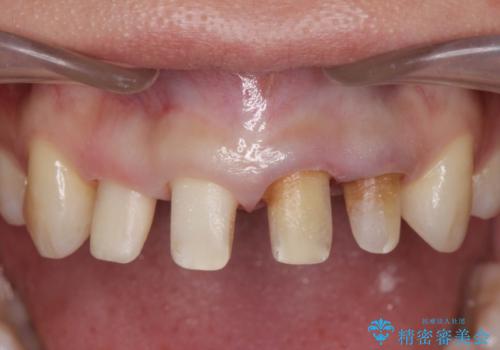

- 神経の死んでしまっている前歯の変色の改善を求めて来院されました。

根管治療をしたのち時間が経過して変色が目立つ歯と、レジン充填が複数箇所に及んでいる歯も同時にオールセラミック治療を行っていくこととなりました。

- 52.8万円(ジルコニアクラウン×4・仮歯×4)費用は治療当時の料金となります